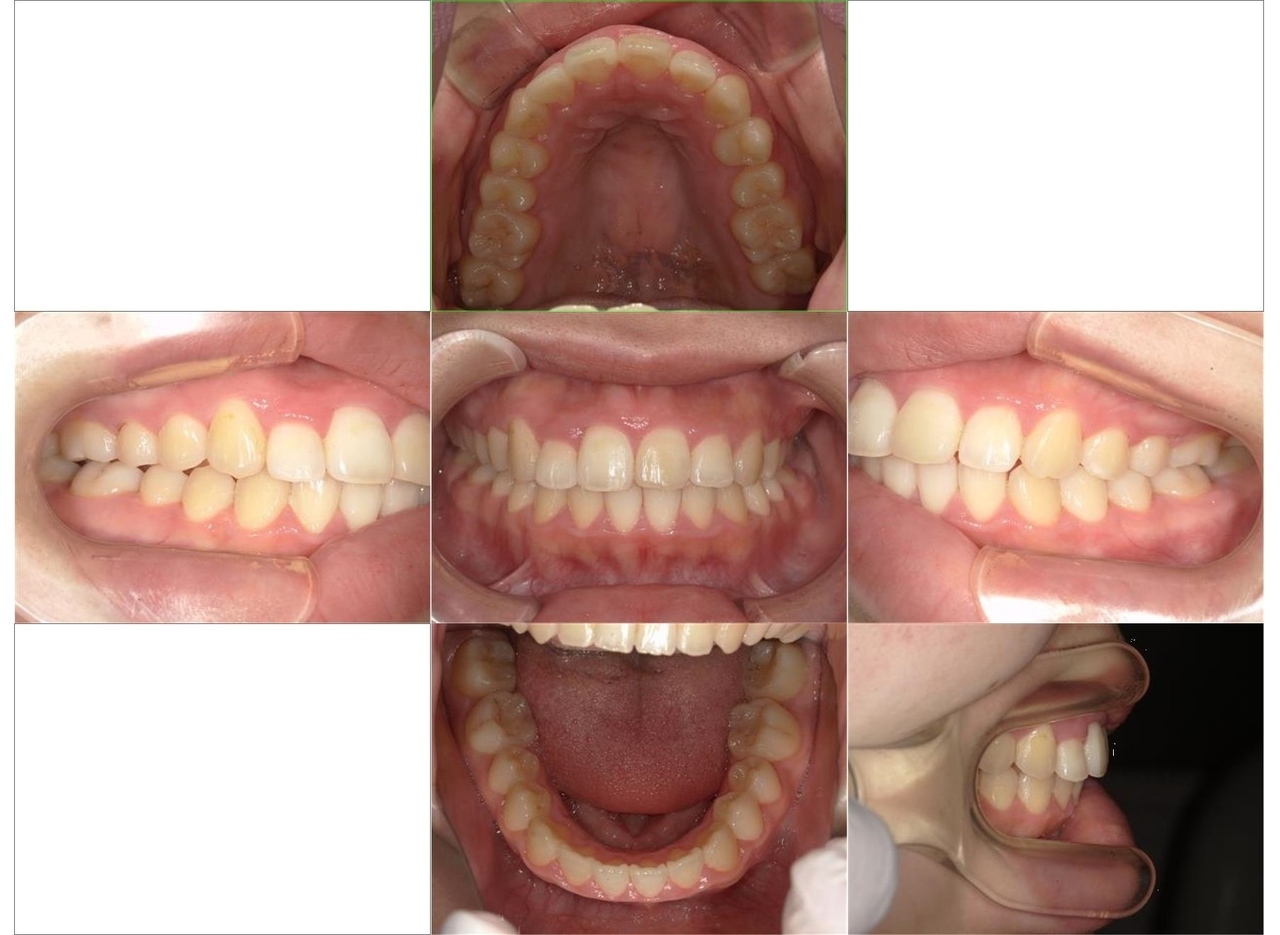

歯ならびの改善を主訴に来院されました。上顎右側に乳歯

(子供の歯)が残存している状態でした。また、下の歯に叢生がありました。患者さんとカウンセリングを行い、マルチブラケット装置によるワイヤー矯正治療を行いました。

はじめに、乳歯の抜歯を行い、乳歯を抜歯したスペースに永久歯を配列しました。また、舌側に位置していた永久歯も上顎の歯列に配列しました。全体の歯の配列が整ってきたので、顎間ゴムにて咬合の緊密化を行い、矯正治療を終了しました